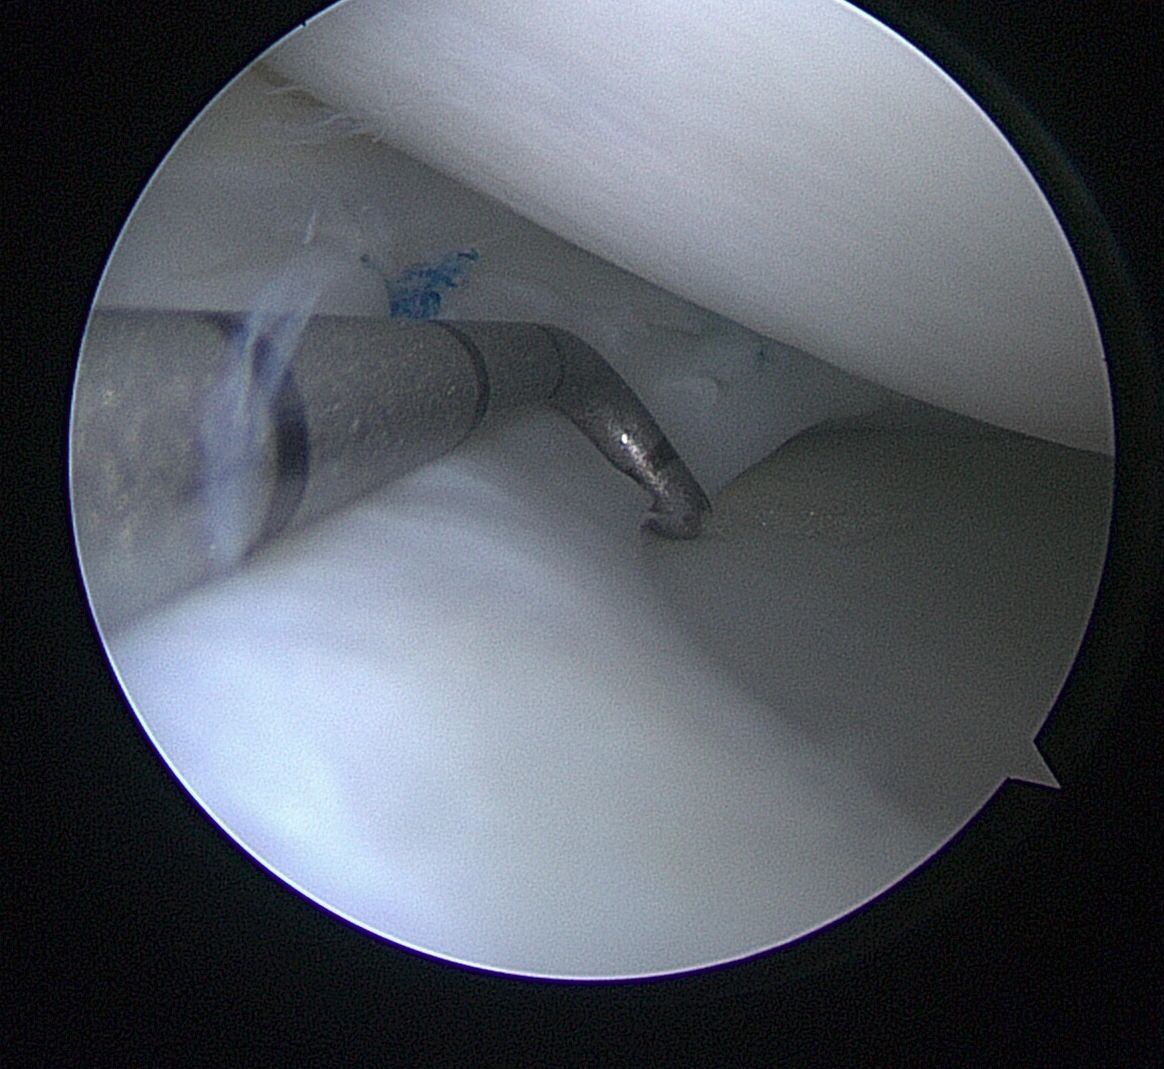

- Meniscus Surgery

- Meniscus Surgery 2